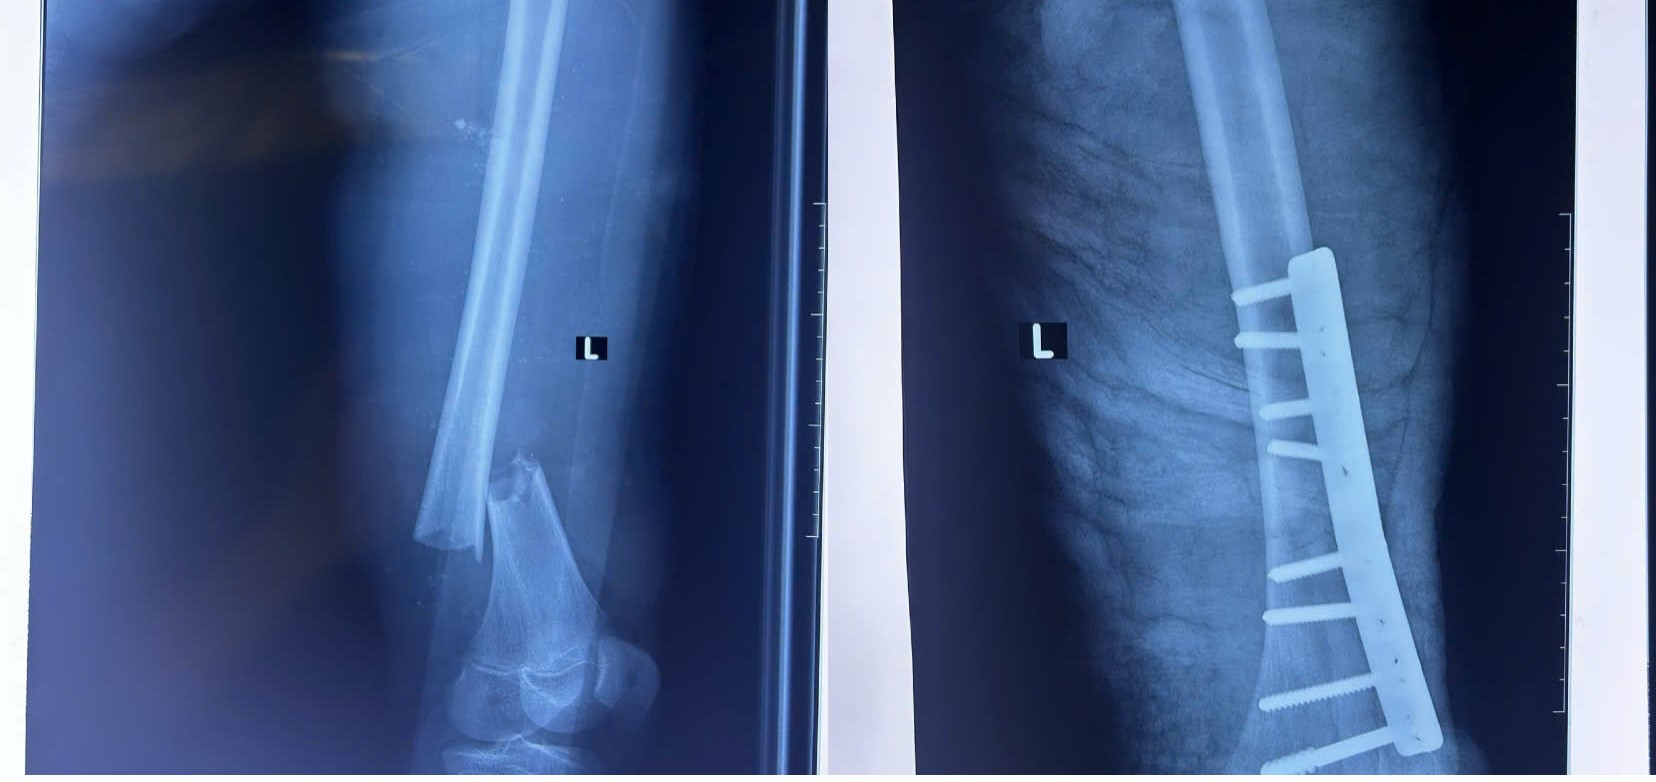

GIỮ LẠI CHÂN CHO NAM THANH NIÊN SAU TAI NẠN GÃY 1/3 DƯỚI XƯƠNG ĐÙI KÈM TẮC MẠCH

Bệnh viện Đa khoa tỉnh Quảng Ngãi đã thực hiện thành công ca phẫu thuật đặc biệt, giữ lại được chân trái của bệnh nhân do tai nạn giao thông nghiêm trọng. Đây là một ca phẫu thuật phức tạp liên quan đến việc kết hợp xương và nối lại động mạch đùi cấp cứu, giúp tái lập lưu thông máu và ngăn ngừa nguy cơ cắt cụt chi.